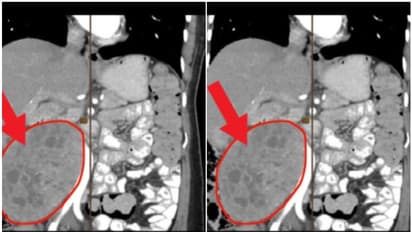

മനാമ: ബഹ്റൈനില് 55കാരിയുടെ വയറ്റില് നിന്ന് രണ്ട് കിലോ ഭാരമുള്ള മുഴ നീക്കം ചെയ്തു. കിങ് ഹമദ് യൂണിവേഴ്സിറ്റി ആശുപത്രിയില് വെച്ചാണ് സ്ത്രീയുടെ ശസ്ത്രക്രിയ നടത്തിയത്. കണ്സള്ട്ടന്റ് ജനറലും ബാരിയാട്രിക് സര്ജനുമായ ഡോ. അബ്ദല് മൊനെയിം അബു അല് സെല്ലിന്റെ നേതൃത്വത്തിലാണ് രണ്ട് മണിക്കൂര് നീണ്ട സങ്കീര്ണമായ ശസ്ത്രക്രിയ പൂര്ത്തിയാക്കിയത്.

വയറുവേദനയുമായാണ് സ്ത്രീ ആദ്യം എത്തിയത്. രണ്ട് മാസത്തിനിടെ പെട്ടെന്ന് ഭാരം കുറഞ്ഞതായും സ്ത്രീ പറഞ്ഞു. ക്ലിനിക്കല് പരിശോധനയിലും കളര് ടോമോഗ്രഫിയിലും സ്ത്രീയുടെ വയറ്റില് മുഴ ഉള്ളതായി കണ്ടെത്തി. കാലം കഴിയുന്തോറും മുഴ അപകടരമാകുന്നതാണെന്ന് ബയോപ്സി റിപ്പോര്ട്ടില് വ്യക്തമാകുകയും ചെയ്തു. തുടര്ന്നാണ് ശസ്ത്രക്രിയ നടത്തി ഇത് പുറത്തെടുത്തത്. കണ്സള്ട്ടന്റ് ജനറല് സര്ജന് ഡോ. ഇജാസ് വാനി, കണ്സള്ട്ടന്റ് വാസ്കുലാര് സര്ജന് ഡോ. റാനി അല് മൊയാറ്റസ് ബില്ലാ അല് അഘ എന്നിവരും ശസ്ത്രക്രിയ നടത്തിയ സംഘത്തിലുണ്ടായിരുന്നു. ശസ്ത്രക്രിയയ്ക്ക് ശേഷം സുഖം പ്രാപിച്ച 55കാരി നാലു ദിവസങ്ങള്ക്ക് ശേഷം ആശുപത്രി വിട്ടു.